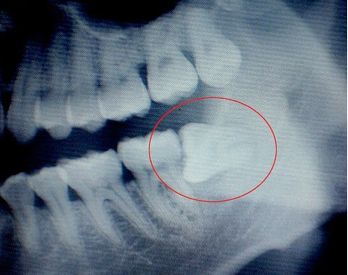

不一定。智齿不一定非得拔掉,智齿阻生分好多种,比如说近中阻生,远中阻生,骨内阻生等等,我们一般只拔出有症状表现的智齿,比如说经常引起发炎,经常引起智齿旁边的牙齿龋坏等,在这种情况下我们一般要求拔出智齿,还有拔出智齿的时候经常要避开月经期,因为在月经期的时候拔牙一般出血都是比较多,而且容易引起感染等症状,还有一般打麻药比较好的时候,拔智齿一般是没有疼痛的。